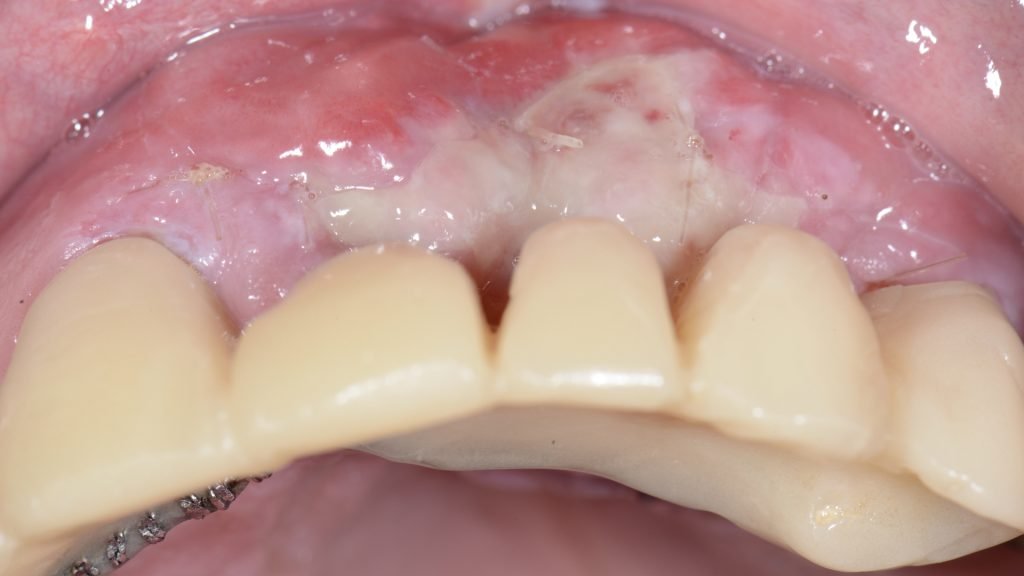

A las 2 semanas se retiran las suturas y se observa una capa de fibrina sobre la que se aplicó un gel de clorhexidina durante 2 semanas más sin mayor inconveniente (Figura 14).

Durante los dos próximos meses se prosiguió con la modificación de los pónticos hasta conseguir el perfil de emergencia deseado (Figura 15).